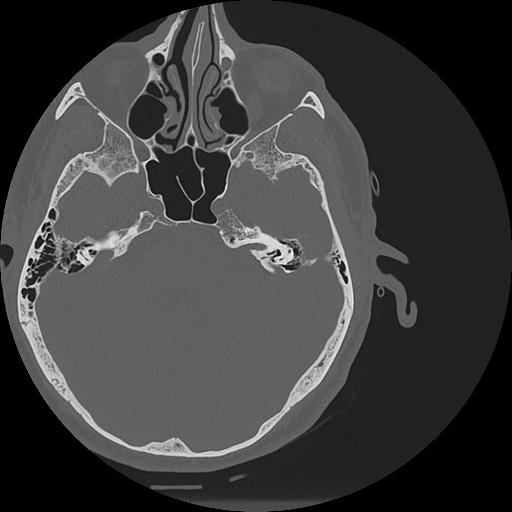

7 HUESO,,Vol,0.5,HUESO,,